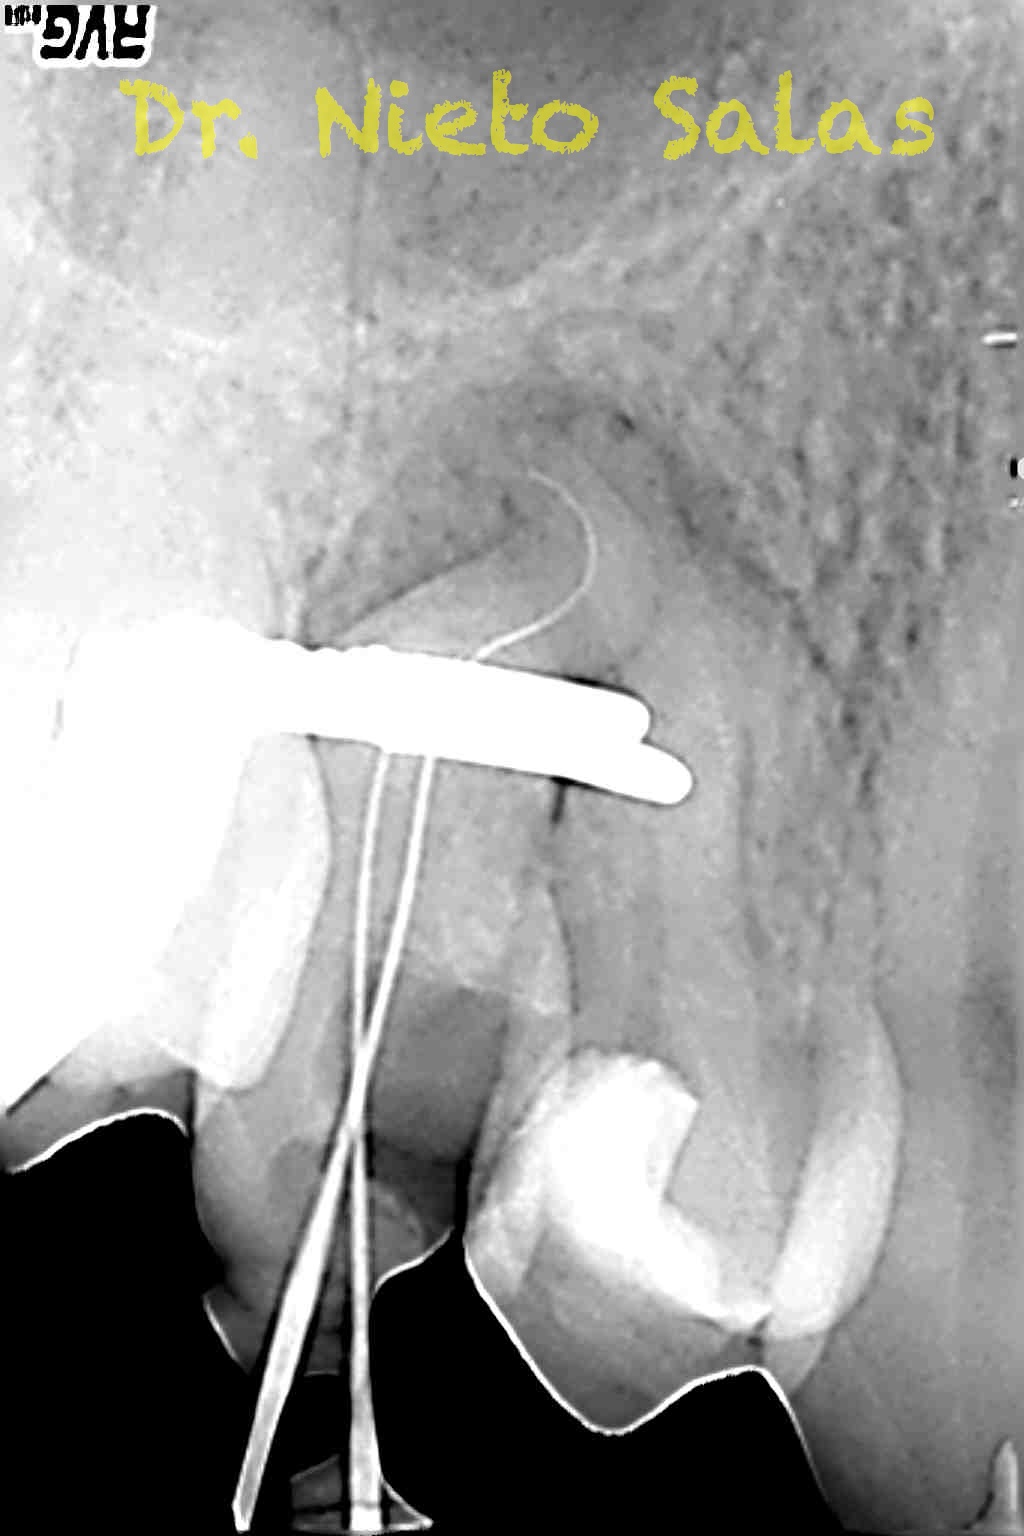

La obturación la haremos con el sistema de condensación vertical por ola continua de Buchanan.

Conseguiríamos un sellado de esta manera en el caso A:

Y  de forma muy similar en el caso B; en este caso el paciente vino a la revisión a los 9 meses evidenciado el éxito en el tratamiento:

La verdad, no me planteé la posibilidad de la obturación con Thermafil, se trataba de un caso con un sistema de conductos con un itsmo coronal, y pienso que la obturación con sistema de ola continua me garantizaba un mejor sellado.